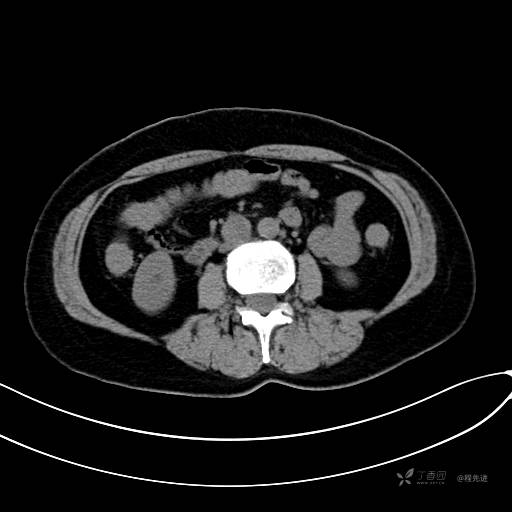

CT增强静脉期